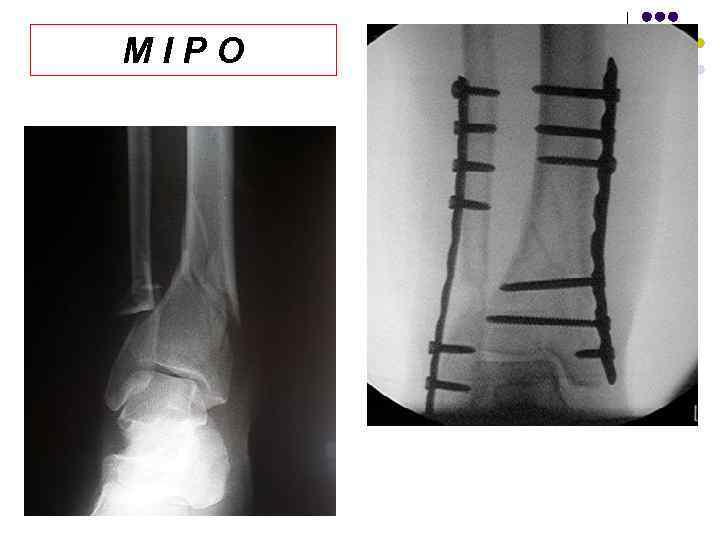

MIPO MIPO